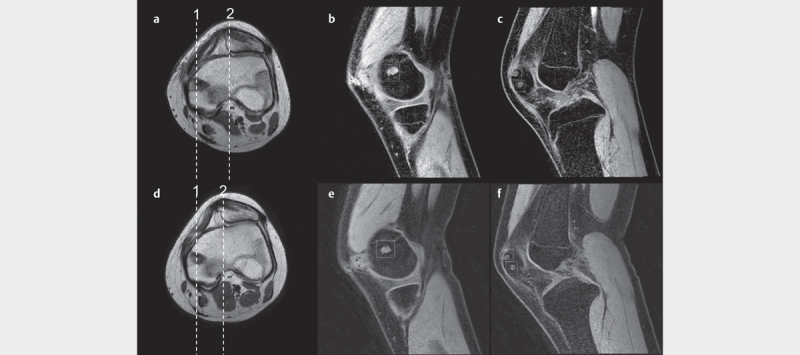

The resumption of blood flow is an important factor in the remodeling process of the graft. The purpose of this study is to evaluate hemodynamic changes after medial patellofemoral ligament (MPFL) reconstruction using magnetic resonance angiography (MRA) as the evaluation of graft remodeling. Eleven knees that underwent anatomical MPFL reconstruction with the semitendinosus tendon were studied. We evaluated the blood flow around the bone tunnel wall in the arterial phase using MRA approximate 3 months and 1 year after surgery. Clinical and radiological evaluations were also analyzed. MRA showed an inflow vessel into the bone tunnel wall from the medial superior genicular artery on the femoral side, and from the articular branch of the descending genicular artery and the medial superior genicular artery on the patellar side. This contrast effect was decreased at 12 months after surgery in all cases. The clinical scores improved from baseline one year postoperatively. We revealed the blood flow to the bone tunnel wall after anatomical MPFL reconstruction is detected by MRA. The blood flow started within 2 or 3 months postoperatively and was sustained for 12 months. This study supported remodeling of the graft continues 3 months after surgery when the conformity of the patellofemoral joint stabilizes.